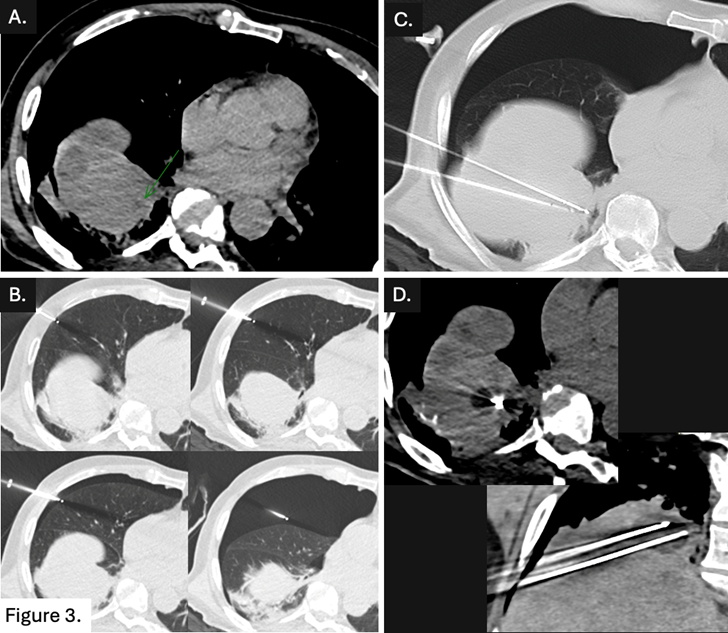

La lésion n'étant pas visualisée en échographie, un guidage scanner a été réalisé (𝗙𝗶𝗴𝘂𝗿𝗲 𝟯. 𝗔).

Création d'un pneumothorax droit intentionnel au 𝗖𝗢𝟮 à l’aide d’une aiguille de 𝗩𝗲𝗿𝗲𝘀𝘀 (𝗕) pour permettre une ponction transthoracique avec deux aiguilles de cryothérapie (𝗖, 𝗗).